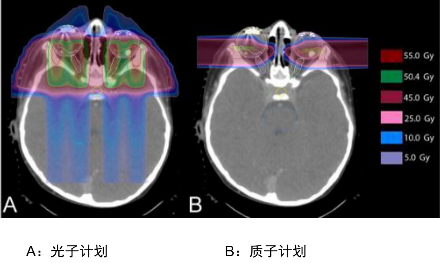

解析:这个是儿童颅咽管癌的IMRT(上图:调强放疗,一种传统放疗的高端模式)与质子治疗(下图:Proton Therapy)的照射剂量分布比较,我们看箭头的指示,传统放疗照射剂量波及的范围很大,虽然颜色很淡(蓝色表示剂量低,黄色表示剂量高),但是需要多个方向同时照射才能达到肿瘤部位的致死剂量,对病灶周边正常组织的危害很大,容易引起严重的副作用,而质子治疗对健康组织的影响会小很多。